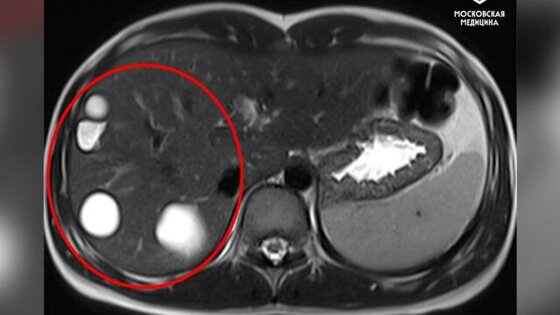

В рамках операции врачи, используя лапароскопию, удалили из печени девочки пять паразитарных кист. Пациентку выписали спустя 5 дней.